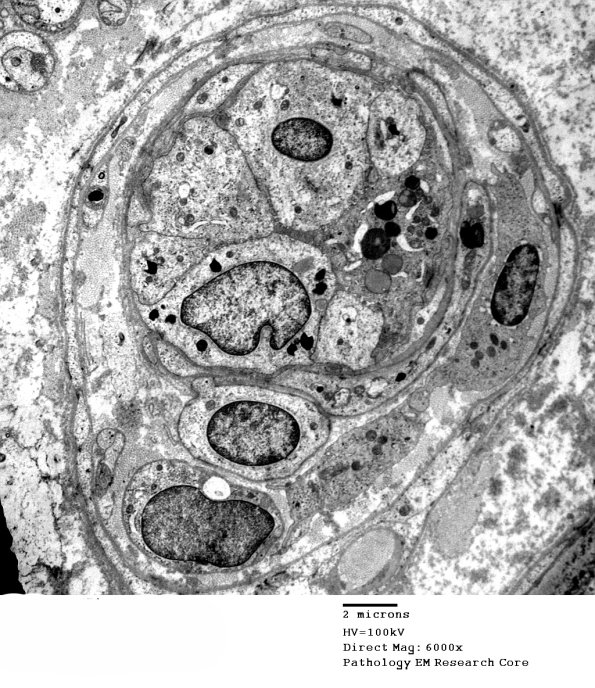

The endothelial cells of this endoneurial venule show membranous and paracrystalline inclusions. (electron micrograph)